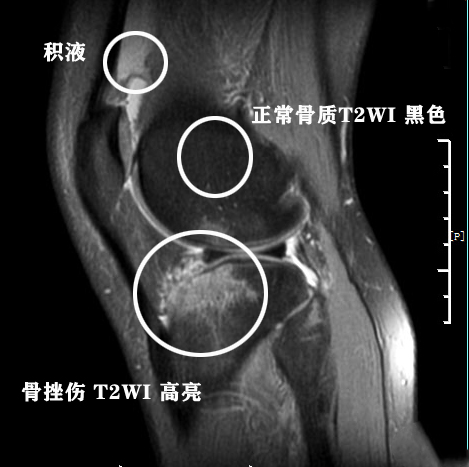

第一,股骨髁内见片状异常信号灶,边界模糊,T1WI略低信号,T2WI略高信号,未见明显骨折线影像。这个患者我们并不知道病史,但是从这个报告单谢医生分析这个患者应该受到了膝关节的撞击或者从高处挑落导致了关节骨与骨之间的撞击,但是力量没有达到使骨头折断的强度,但是导致了关节内骨松质的微骨折,微骨折以后会出血,所以出现了这种情况。一般影像是下图这样的:

第四,周围软组织肿胀。软组织肿胀的影像主要是T2像更加明确,肿胀的影像和积液影像差别不大,但是积液的影像是单纯的一片高亮影像,而软组织肿胀是混杂的、不均匀的影像。